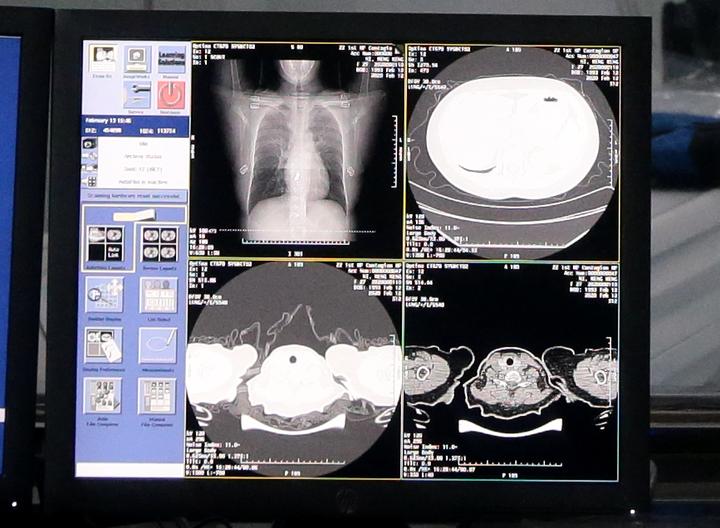

目前基于深度学习的计算机视觉技术在医疗诊断上已经取得了很好的效果。倘若自动化诊断能够应用在对抗新冠肺炎的“战场”上,会使前线医护工作人员的工作压力大大减少。比如最近阿里达摩院研发出来的算法,他们利用5000多个病例的CT样本作为训练数据,最终模型对于新冠肺炎的诊断准确度可以达到96%,并且确诊时间仅需要20秒。

CT样本(图片来自网络)

不过,此类技术最大的问题是机器的学习需要依赖于大量的历史数据,这意味着在疫情早期做到成熟地应用是非常困难的。因此,如何将以往的类似疫情(例如SARS等)中所积累的医疗资源和数据拓展并且应用到新的疫情上,也就是深度学习里面常说的迁移学习,我想这是未来一个值得研究的方向。